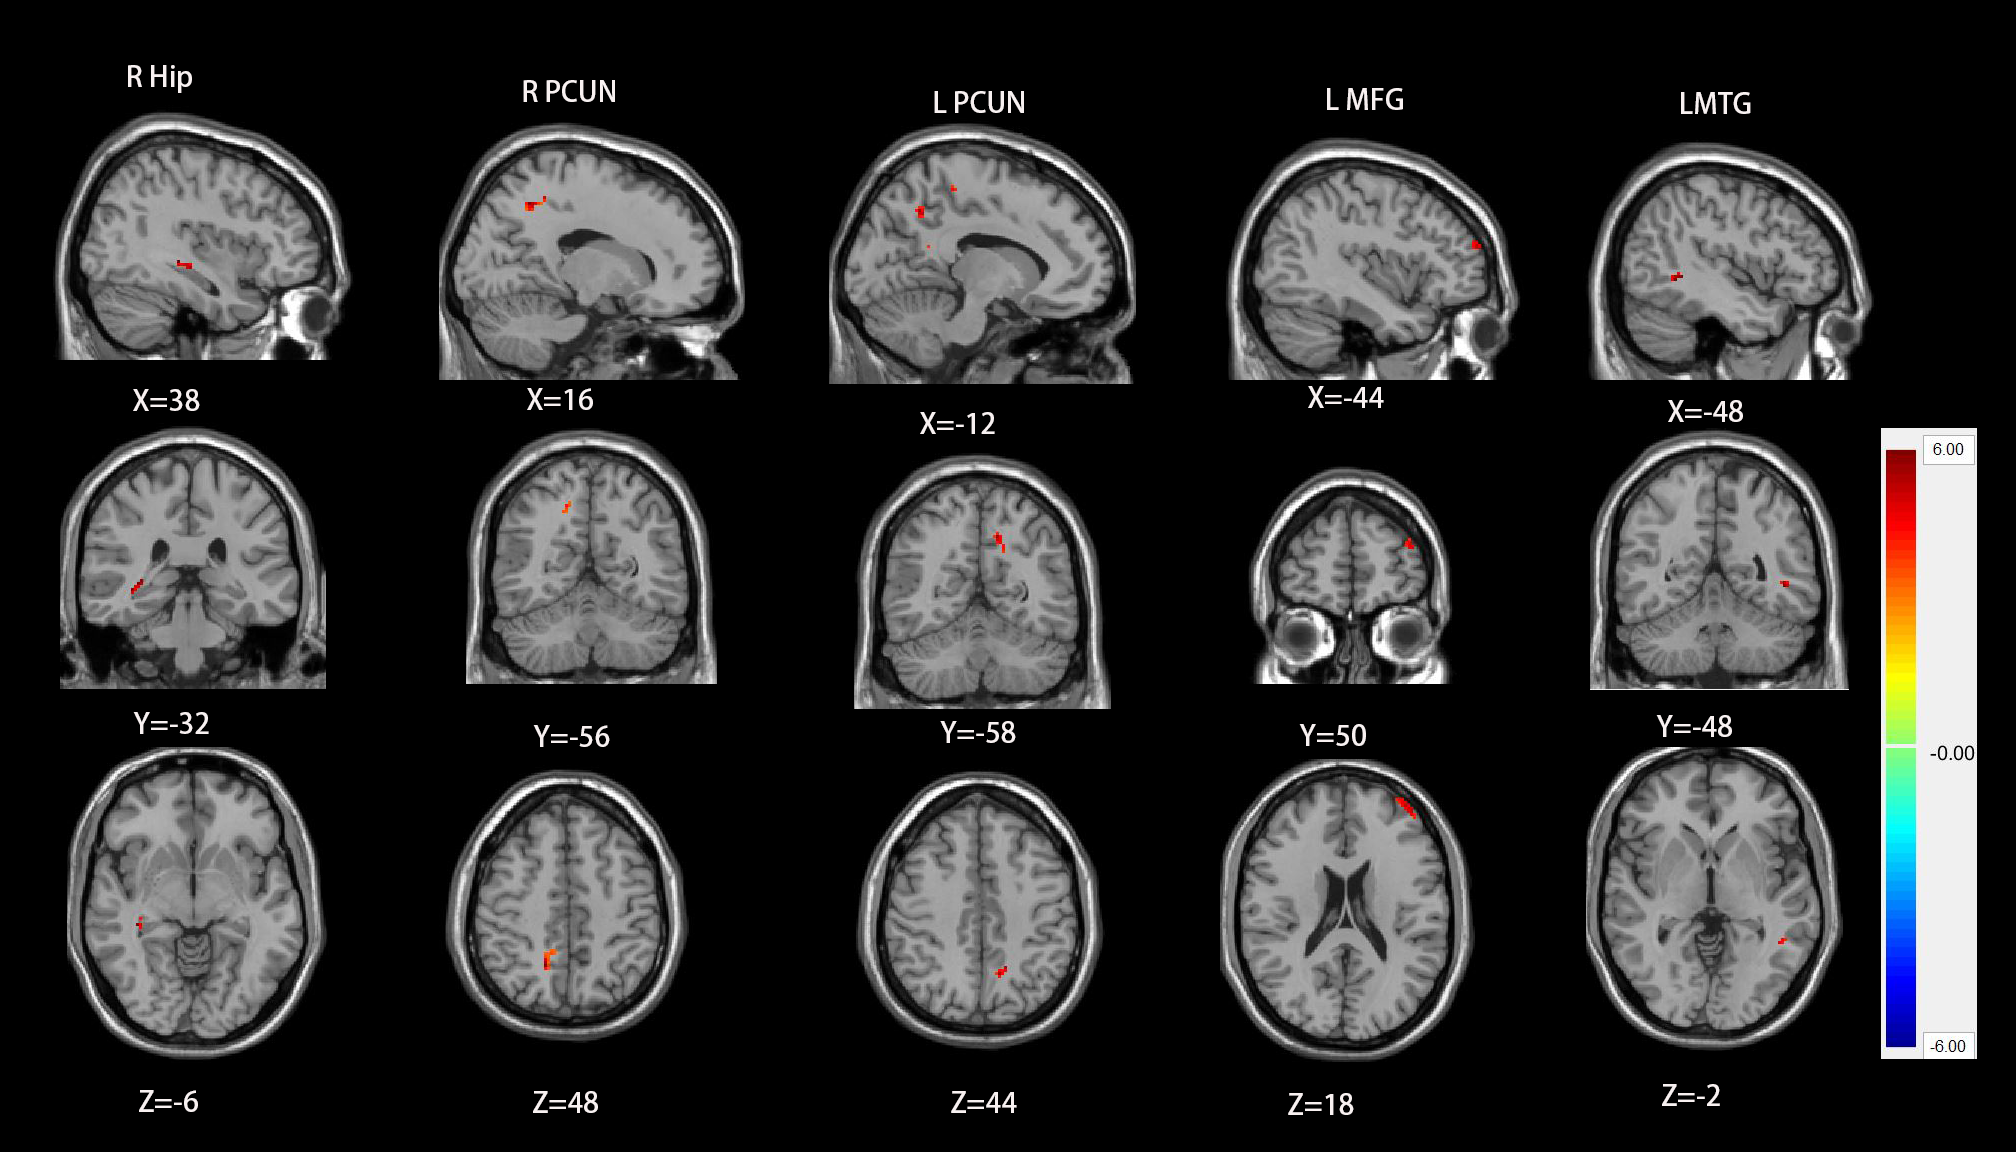

RESULTS: Compared with healthy controls, chronic tinnitus patients with hearing loss showed a significantly increased ALFF values in the right hippocampus, left middle temporal gyrus (MTG), left middle frontal gyrus (MFG), and bilateral precuneus, and a significantly increased ReHo values in left PAC, bilateral MTG, left superior temporal gyrus (STG), right amygdala and left angular gyrus (AG). Based on FC analysis, the left PAC showed reduced functional connectivity with non-auditory brain regions including the right MFG, right cingulate cortex, right cuneus and left cerebellum in the groups of chronic tinnitus with hearing loss compared with healthy controls.

Figure2 chronic tinnitus patients showed a significantly increased ReHo values in left PAC, bilateral MTG, left STG, right amygdala and left AG